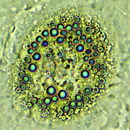

Bildunterschrift: Cholesterin-Ablagerungen in einer Arterie (Bild 1) und Fettzellen im Körper (Bild 2).

Bildquelle: Karl-Franzens-Universität Graz